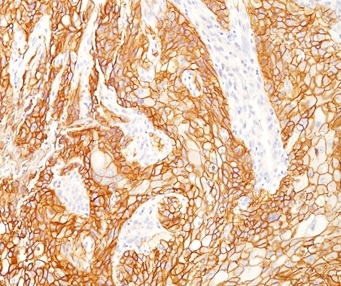

Formalin-fixed, paraffin-embedded human lung SqCC stained with EGFR Mouse Monoclonal Antibody (GFR/2341).

This MAb recognizes a protein of 170kDa, identified as EGFR. EGFR is type I receptor tyrosine kinase with sequence homology to erbB-1, -2, -3 -4 or HER-1, -2, -3 -4. It binds to Epidermal Growth Factor (EGF), Transforming Growth Factor-a (TGF-a), Heparin-binding EGF (HB-EGF), amphiregulin, betacellulin and epiregulin. EGFR is overexpressed in tumors of breast, brain, bladder, lung, gastric, head & neck, esophagus, cervix, vulva, ovary, and endometrium. It is predominantly present in squamous cell carcinomas.